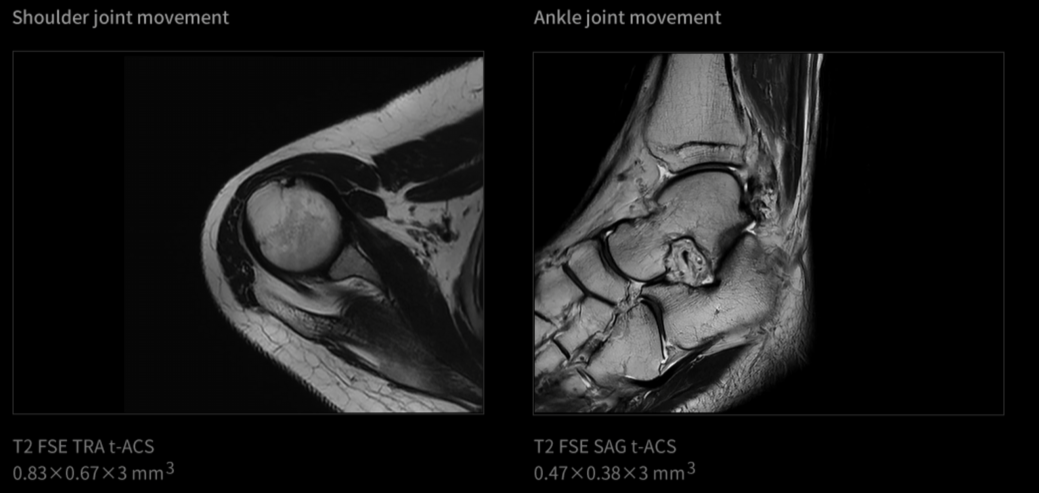

Otevřený tunel o průměru 70 cm, gradient 100 mT/m a 200 T/m/s umožňují ultra-rychlou uzávěrku a plynulé snímání pohybu.

Od vzniku magnetické rezonance je pohyb jednou z největších výzev při zobrazování. Celá desetiletí byly v tomto odvětví zkoumány různé technologie pro „zmrazení pohybu“. Inovace uMR Ultra dnes slibuje svět MRI bez omezení pohybu – oblast, ve které můžeme pozorovat skutečný stav lidského těla. Jelikož otevíráme novou dimenzi zobrazování pomocí MR, je komplexní transformace diagnostických standardů nevyhnutelná.